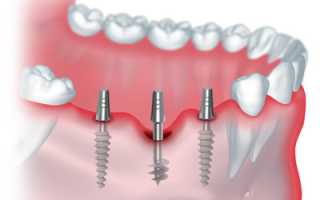

Процедура базальной имплантации зубов позволяет одноэтапно установить титановый стержень в глубокие и твёрдые слои челюсти, избегая различные формы адентии.

По итогу манипуляции встроенный корень одномоментно нагружается зубным протезом. Это позволяет практически сразу восстановить жевательную функцию в ротовой полости в полном объёме и вернуть обычные нагрузки при приёме пищи.

- Моделирование — врач производит 3D модель импланта с помощью компьютера: выбирает размер и форму, соответствующие особенностям полости рта.

- Вкручивание стрежня — на место удалённого зуба устанавливается стержень. Для наилучшей фиксации врач может сделать прокол. Продолжительность процедуры составляет 30 минут.